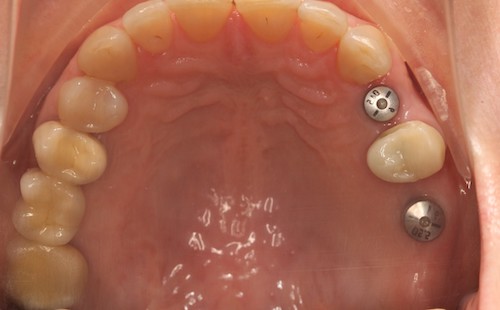

Ляшев Илья Николаевич успешно провел имплантацию 5 ед системы Astra Tech с одномоментным наращиванием костной ткани в области отсутствующих зубов. после приживления имплантов были выполнены временные коронки, а затем и постоянные как на имплантах, так и на собственных зубах. Еще предстоит работа с верхним зубным рядом, но уже сейчас получилось повысить качество пережевывания пищи.

После